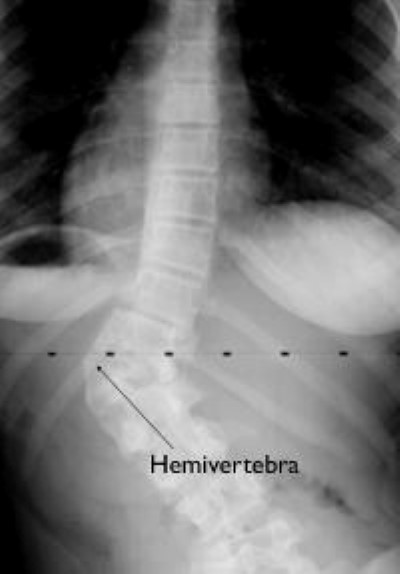

congenital scoliosis curve caused by hemivertebra

This adolescent girl's curve and the hemivertebra causing it show up clearly on X-ray.

Courtesy of Scottish Rite for Children, Dallas

As the spine forms before birth, part of one vertebra (or more) may not form completely. When this occurs, the abnormality is called a hemivertebra (hemi = half), and it can produce a sharp angle in the spine. The angle can get worse as the child grows.

This abnormality can happen in just one vertebra or in many throughout the spine. When there is more than one hemivertebra, they will sometimes balance each other out and make the spine stable.